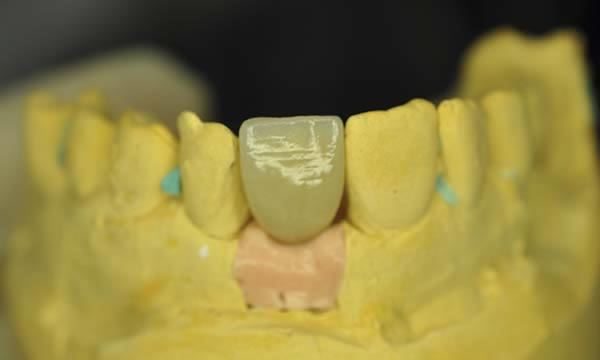

Case G

A failed apicectomy in the UL1 was diagnosed after a history of labial draining discharge and mobility. The patient was referred to us for treatment and a diagnostic wax up was used to discuss the proposed finished crown, estimated gingival margin position and crown height with the patient.

A tooth bourn position guide allowed for predictable implant placement within the aesthetic zone. Collaboration with with Smile Dental Laboratory and clinical pictures helped to produce a great shade match and natural looking result.

During Treatment